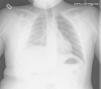

Caso n.° 1: niña de 13 años con 2 dispositivos de derivación ventrículo-peritoneales (DVPT) por hidrocefalia neonatal, con dolor abdominal de 15 días de evolución, fiebre, vómitos y cefalea. Tras varias visitas al hospital se sospecha abdomen agudo, objetivándose por medio de tomografía abdominal quistes de evacuación pericatéter. En la analítica destacaban 8.900 leucocitos/μl (80% neutrófilos), velocidad de sedimentación globular (VSG) >50mm y proteína C reactiva (PCR) de 36,4mg/dl. Ante la sospecha de infección de la DVPT, se recogieron muestras de LCR (bioquímica normal; cultivos negativos), se externalizaron los catéteres y se inició antibioterapia con vancomicina, cefotaxima y metronidazol, sustituyéndose posteriormente por piperacilina-tazobactam. Únicamente se aisló E. faecalis en la punta del catéter. A los 18 días se recolocaron 2 válvulas de derivación ventriculopleurales (DVPL) (fig. 1), manteniéndose 7 días más el tratamiento antibiótico, con buena evolución.